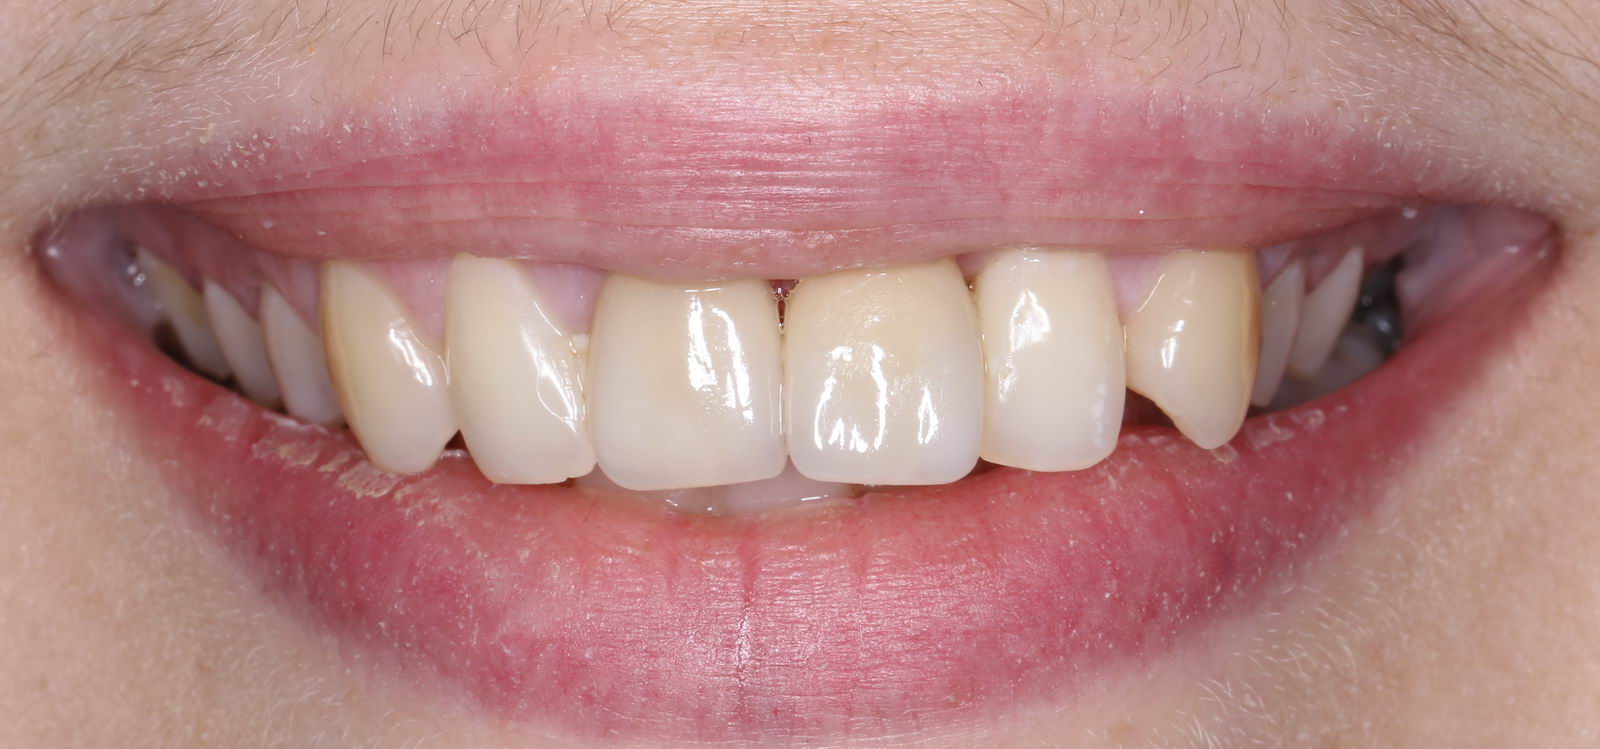

Мы можем удалить его, сразу установить имплантат, в некоторых случаях — сразу с временной коронкой:

Если временную коронку установить невозможно (низкая стабильность имплантата или боковой зуб), можно ограничиться формирователем десны, а для эстетически значимой зоны сделать временный протез с опорой на соседние зубы: